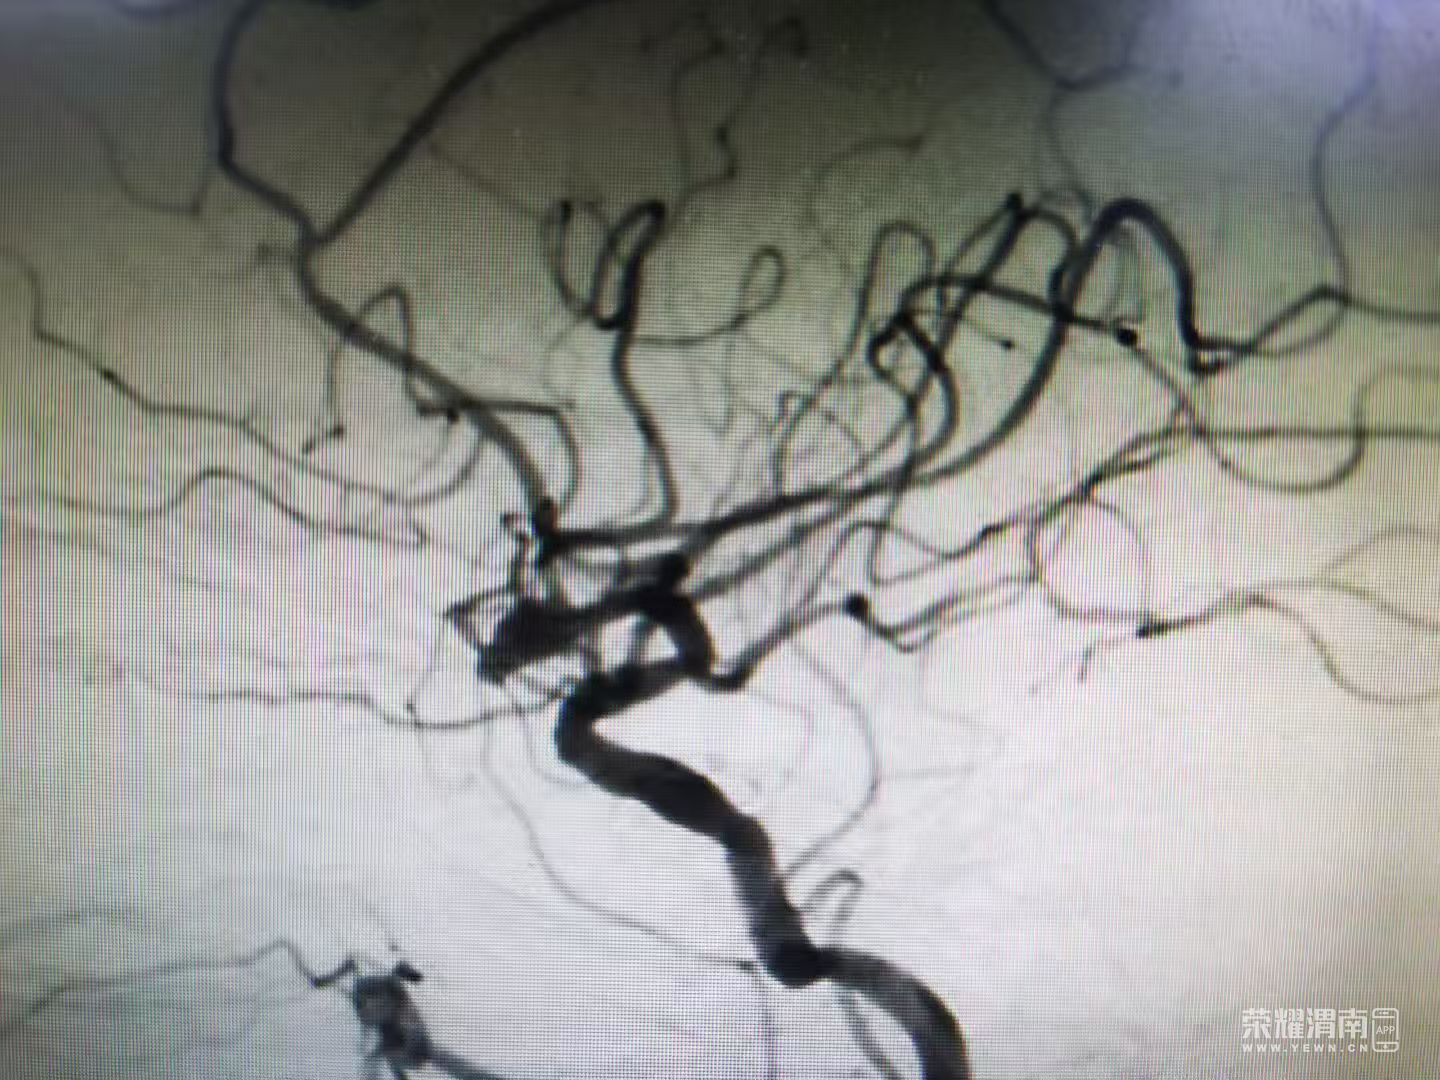

在此基础上,神经外科联合重症医学科、手术麻醉科、介入科组成多学科诊疗小组,通过多次会诊研讨,为患者制定了个体化治疗方案——行动脉瘤支架辅助弹簧圈栓塞术

手术过程中,各科室紧密协作:介入科准确定位动脉瘤,麻醉科全程监测维持生命体征平稳,神经外科顺利完成支架辅助弹簧圈栓塞,成功封闭破裂动脉瘤。术后,重症医学科接力开展全面监护与治疗,帮助患者平稳度过感染期与康复阶段。